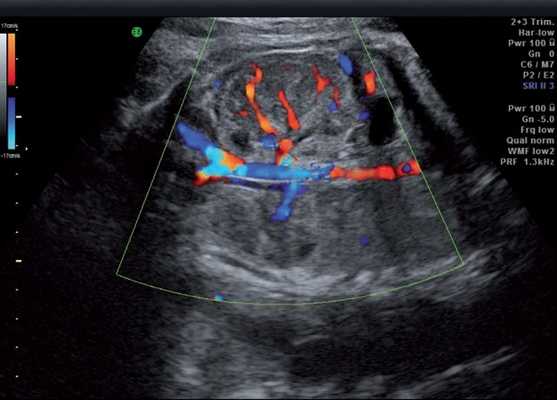

Результаты исследования: размеры плода пропорциональные, соответствуют менструальному сроку беременности. При эхокардиографии особенностей строения сердца у плода не выявлено. При оценке органов мочевыделительной системы обнаружено следующее: правая почка плода нормальных размеров и структуры. Левая почка увеличена до размеров 53х38х46 мм при 95-м процентиле нормативных для срока значений 43х24х23 мм [4] (рис. 1). В структуре почки, преимущественно в верхнем и среднем сегментах, определяется округлое образование без четких контуров, средней эхогенности, приблизительные размеры его 50х35х35 мм. При цветовом допплеровском картировании в образовании визуализируется обширная сосудистая сеть. При допплерометрии индексы сосудистой резистентности (рис. 2) в разных участках образования варьируют в широких пределах (от 0,49 до 0,77).

Рис. 2. Режим цветового допплеровского картирования. Хорошо видны различия в характере васкуляризации нормальной почки и контрлатеральной пораженной почки.

Мезобластическая нефрома - это односторонняя округлая солидная опухоль без капсулы, однородной структуры, иногда содержащая кистозные включения, образующиеся за счет кровоизлияний или очагов некроза. Микроскопически опухоль представлена мезенхимальными клетками, к которым относятся гладкие мышечные волокна и незрелые фибробласты. Кроме того, она может содержать клеточные элементы почечных клубочков и трубочек. Эта опухоль не имеет капсулы и способна к инфильтрирующему росту. Опухоль хорошо васкуляризирована и имеет развитую сосудистую сеть [4].

При ультразвуковом исследовании опухоль Вильмса также выглядит как округлое, хорошо отграниченное образование средней эхогенности. При цветовом допплеровском картировании выраженной сосудистой сети обычно обнаружить не удается. Экстраренальные сочетанные аномалии развития при нефробластоме встречаются редко [9, 10].